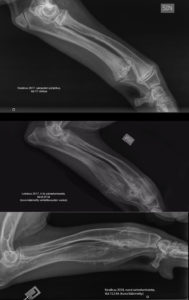

Edelliset röntgenkuvat jaloista on otettu lokakuussa 2017. Silloin sairauden akuutti vaihe oli ohi; olimme juuri pystyneet jättämään kipulääkkeet pois ja uudisluun sulatteluvaihe pääsi alkamaan. Koira pystyi palailemaan normaaliin kivuttomaan arkeen ja liikkumiseen.

Ja tältä jalka vasen etujalka näyttää nyt röntgenin läpi (ikää 15,5 kk):

Tässä vielä yhdistettynä vertailukuvat kaikista rtg-kuvista, jotka on otettu kesäkuussa 2017, lokakuussa 2017 ja kesäkuussa 2018.